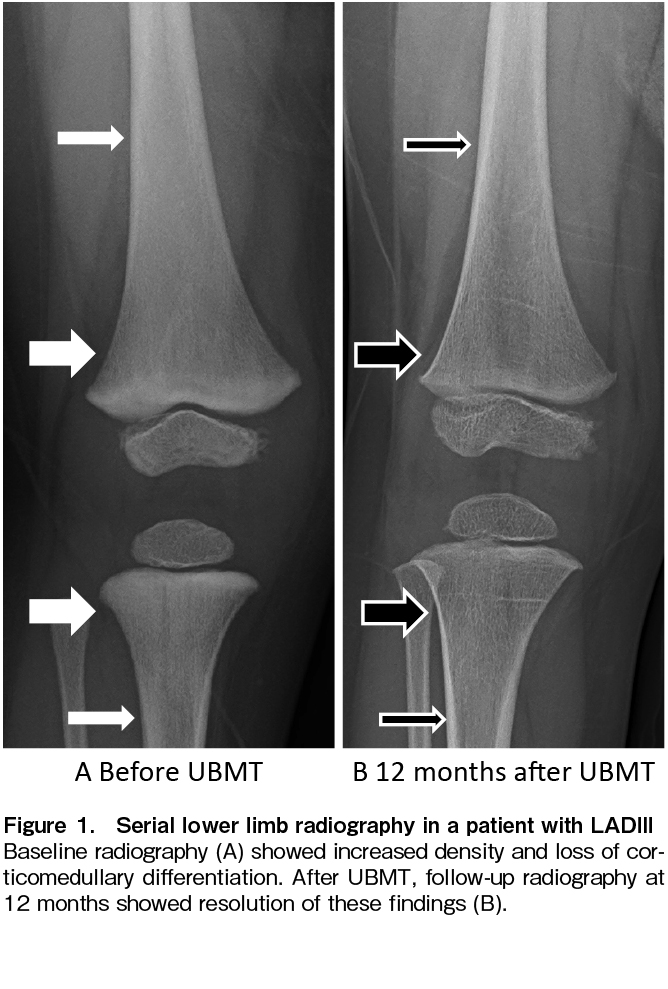

LADIII was diagnosed as follows: Neutrophils and monocytes were stimulated with fMLP and PMA (PKS analog) to demonstrate inducible defects in β2 integrin. Western blotting revealed defective kindlin-3 expression in platelets. Genetic analysis detected the homozygous variant kindlin-3 c.918 G>A, p277 Trp>stop. A vector expressing this kindlin-3 variant was transfected into 293T cells and it was confirmed to be responsible for the defective kindlin-3 expression. Before transplantation, the metaphysis of the femur and tibia showed mild sclerosis, increased radiodensity, and absence of the trabecular pattern (thick arrows, Figure 1A); corticomedullary differentiation was diminished in the diaphysis (thin arrows, Figure 1A). These findings reflected the complications of osteopetrosis.

Donor cell engraftment was examined by the STR method on day 14, and 55.0% of the donor-type cells were detected by using BM cells, while only 5.9% and 20.8% were detected by using PB T cells and NK cells, respectively. To activate donor-derived T cells against imminent graft rejection, tacrolimus was reduced to one-third of the starting dose on day 15 and discontinued on day 19 after confirming no response in clinical symptoms upon tapering. A fever of 38.1℃ appeared on day 20 and intensified to 39.9℃ on day 23 with skin flushing but without fixed maculopapular rash. Tacrolimus was restarted at 0.015 mg/kg/day on day 24. The fever resolved on day 27. However, donor T cells remained at 8.7% in PB on day 28, and tacrolimus was stopped again on day 30. Fever as high as 38.9℃ developed again with mild skin eruption, and donor cells increased to 50.3% in T cells, 79.8% in NK cells, and 100% in granulocytes on day 34. The donor chimerism in BM increased to 85.1% on day 28 and reached 100% on day 56. From day 82 until 6.5 years after UBMT, all chimeric studies using PB samples, separated into granulocytes, T cells, and NK cells, consistently showed 100% donor-derived cells. No serious complications such as infections, bleeding, or GVHD were observed. Serial skeletal X-ray studies revealed a reversal of generalized bony sclerosis, probably due to the remodeling process without new sclerotic bone formation (Figure 1B). For 6.5 years after UBMT, the patient has been free of infection and bleeding with normal growth and development.

LADIII has been reported to be accompanied by osteopetrosis in 32% of patients6, which has been shown to make HSCT more challenging via an increase in the incidence of transplant-related morbidities such as GF. The 5-year survival rates among recipients with infantile osteopetrosis were 62% after HLA-matched sibling transplantation and 42% after alternative donor transplantation. GF was the most common cause of death, accounting for 50% of deaths after HLA-matched sibling transplantation and 43% of those after alternative donor transplantation7. Osteopetrosis associated with LADIII has also been shown to improve after HSCT2 and, in the present case, the radiographic findings confirmed such improvement (Figure 1B).